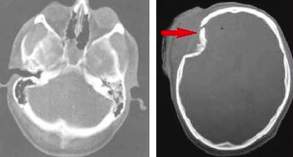

Dijagnoza se postavlja CT-om

Slika: CT snimak mozga – strelica pokazuje subduralni hematom

(ugrušak ispod tvrde ovojnice mozga – dura mater)

Treba imati u vidu da je izmedju 2 i 6 nedelje hematom izodenzan sa

susednim mozdanim tkivom i pokazuje samo pomeranje bočne komore. U kasnijoj

fazi hematom je hipodenzan na CT snimku. NMR je koristan kod subakutnih